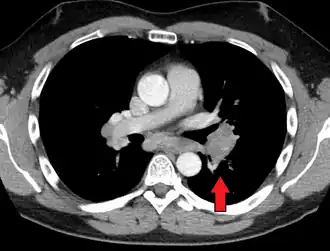

CT scan of the chest showing lymphadenopathy (arrows) in the mediastinum due to sarcoidosis

Diagnosis of sarcoidosis is a matter of exclusion, as there is no specific test for the condition other than the Kveim-Siltzbach test. To exclude sarcoidosis in a case presenting with pulmonary symptoms might involve a chest radiograph, CT scan of chest, PET scan, CT-guided biopsy, mediastinoscopy, open lung biopsy, bronchoscopy with biopsy, endobronchial ultrasound, and endoscopic ultrasound with fine-needle aspiration of mediastinal lymph nodes (EBUS FNA). Tissue from biopsy of lymph nodes is subjected to both flow cytometry to rule out cancer and special stains (acid fast bacilli stain and Gömöri methenamine silver stain) to rule out microorganisms and fungi.[99][100][12][101]